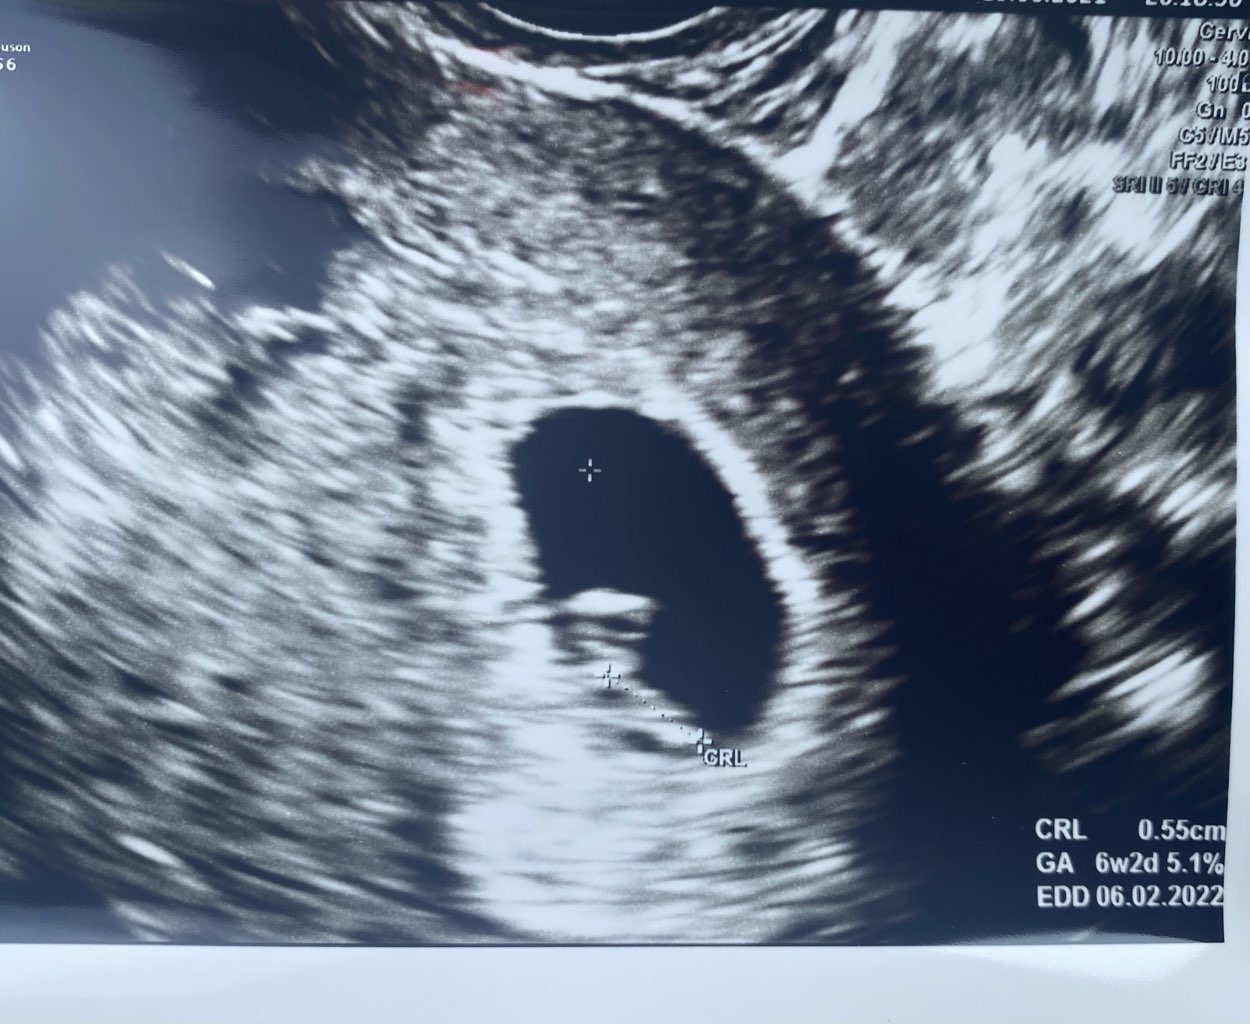

Lekarz nie musi słuchać żeby ocenić ilość uderzę. W usg wykorzystywane jest we wczesnej ciążę motion Mode, jest to obrazowanie bicia serca, na tej podstawie komputer wylicza częstotliwość uderzeń. Nie zmienia to jednak faktu, że wydaje mi się, że 185, uderzeń to wziąz norma, zwłaszcza dla tak młodej ciąży

Ja też się aż wzruszylam i cały dzień czekałam ❤ Widzę jedno dzieciątko. Najważniejsze że to jedno jest silne i zdrowe. Silny Maluszek 🌞 Teraz już bedzie TYLKO DOBRZE. Nawet nie wiesz jak się cieszę! Pewnie wszystkie tu tak samo cieszymy się z Tobą, to w końcu NASZ DZIDZIAK 😘😘😘😘😘

Ja już po, wszystko dobrze 😊 za trzy tygodnie prenatalne 😉 Fajnie się wiercił groszek na usg 🥰

173,3 KB · Wyświetleń: 94